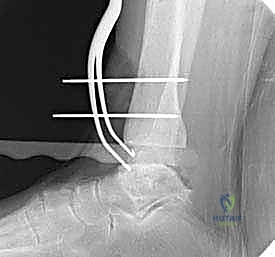

- الأشعة السينية الحاملة للوزن (Weight-Bearing X-rays): هي المعيار الذهبي المبدئي. تظهر تضيق المسافة المفصلية، تكون النتوءات العظمية (Osteophytes)، والتكيسات العظمية (Subchondral cysts).

- الأشعة المقطعية (CT Scan): ضرورية جداً للتخطيط الجراحي، حيث تعطي صورة ثلاثية الأبعاد لحجم العظام وجودتها، وتساعد في تحديد حجم غرسة STAR بدقة.

تعتمد دقة الجراحة على المحاذاة الصحيحة. يتم استخدام أجهزة توجيه متطورة (Jigs) تثبت على عظمة الساق باستخدام دبابيس معدنية. يتم التحقق من صحة الزوايا والمحاور باستخدام جهاز الأشعة السينية المباشر داخل غرفة العمليات (C-arm Fluoroscopy). يضمن الدكتور هطيف أن يكون القطع موازياً للأرض تماماً عند وقوف المريض.